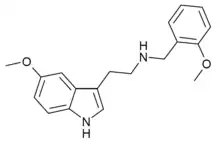

| 5-MT-NBOMe | artificial | 5-OCH3 | H | CH2C6H4(o-OCH3) | 5-methoxy-N-(ortho-methoxybenzyl)tryptamine | 1335331-37-7 |